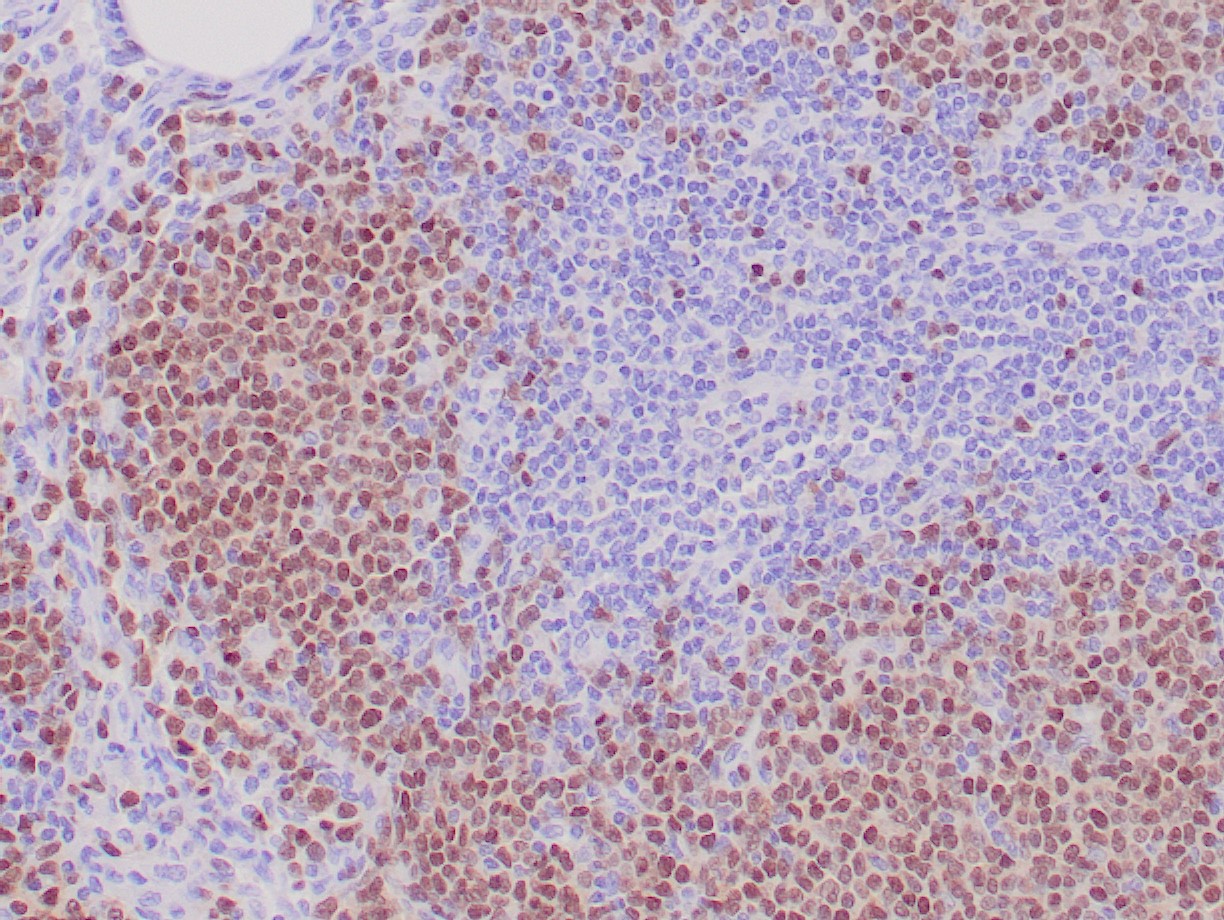

SOX11 is a transcriptional factor normally expressed in embryonic central nervous system but not in adult tissues. Over-expression of SOX11, has been demonstrated in certain malignancies including ovarian cancer, medulloblastoma, and malignant glioma. More recent studies have shown that both SOX11 mRNA and protein are also up-regulated in lymphoblastic lymphoma, Burkitt’s lymphoma, and MCL independent of cyclin d1 status. The first two types of lymphoma are easily distinguished from MCL by morphology and immunophenotype, which makes SOX11 a very useful biomarker for diagnosis of cyclin d1 negative MCL.

Sox11 can be detected in tissue sections by immunohistochemistry. Specimen requirement is a formalin-fixed, paraffin-embedded tissue block or unstained glass slides.